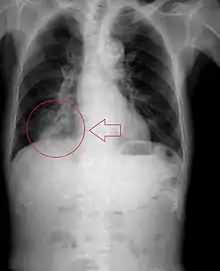

Aspiration pneumonia

Pulmonary aspiration of particulate matter may result in acute airway obstruction which may rapidly lead to death from arterial hypoxemia.[2]

Pulmonary aspiration of acidic material (such as stomach acid) may produce an immediate primary injury caused by the chemical reaction of acid with lung parenchyma, and a later secondary injury as a result of the subsequent inflammatory response.[2]

Pulmonary aspiration may be followed by bacterial pneumonia. Community-acquired aspiration pneumonia is usually caused by anaerobic bacteria, whereas hospital-acquired aspiration pneumonia is more often caused by mixed flora, including both aerobic and anaerobic bacteria.[2]

Pulmonary aspiration resulting in pneumonia, in some patients, particularly those with physical limitations, can be fatal.